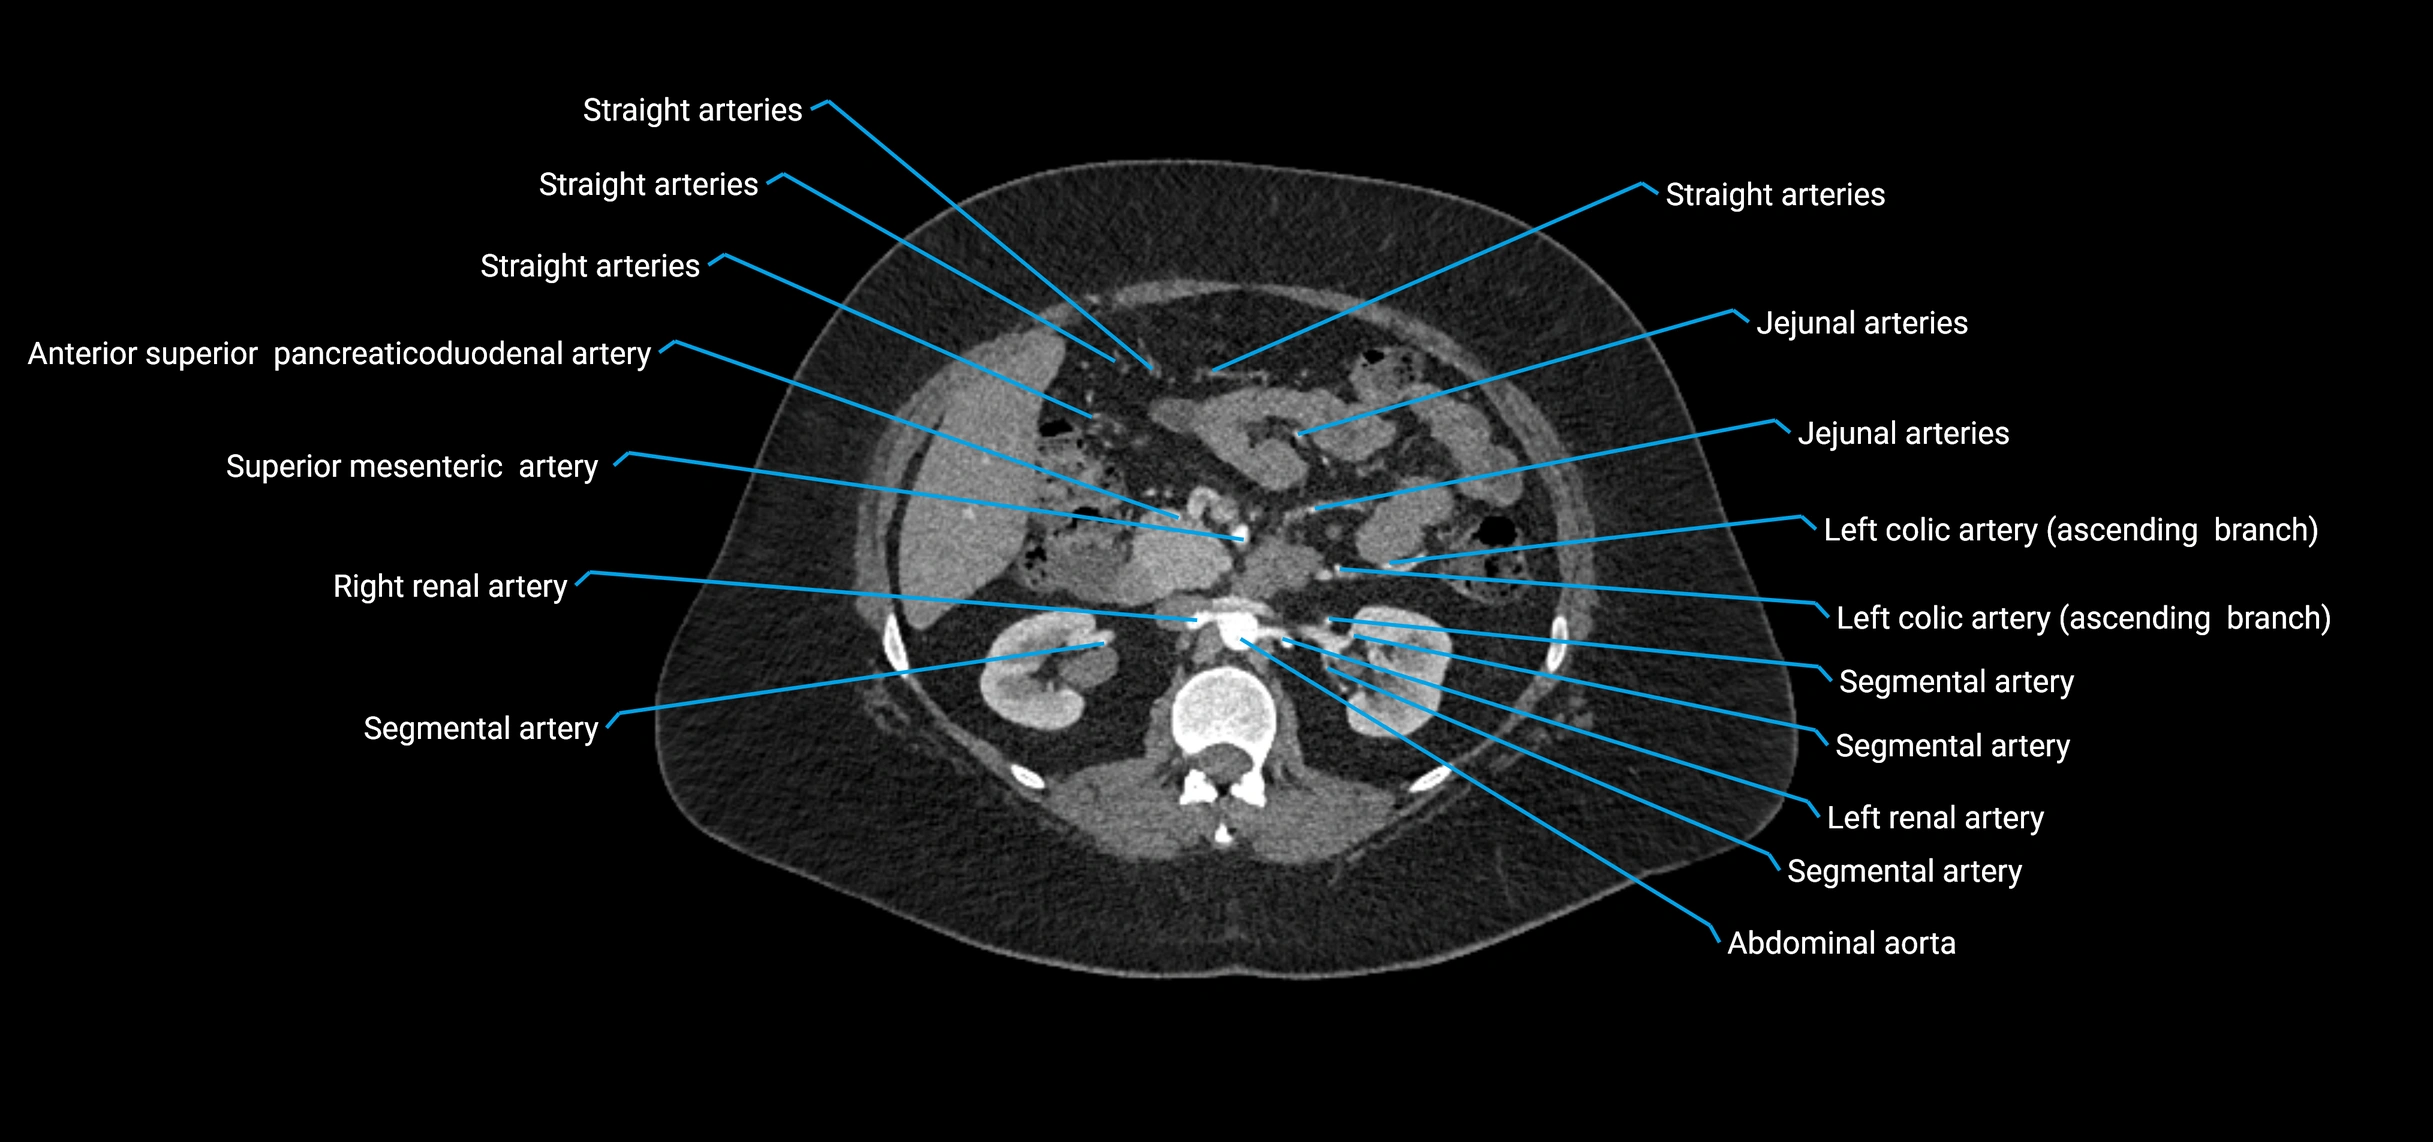

• Unpaired visceral branches: celiac trunk, superior mesenteric artery (SMA), inferior mesenteric artery (IMA)

• Paired visceral branches: middle suprarenal arteries, renal arteries, gonadal arteries (testicular or ovarian)

Contrast-enhanced CT (CTA):

• Gold standard for abdominal aortic imaging

• Provides excellent detail of lumen, wall, aneurysm, thrombus, and branch vessels

• Multiplanar and 3D reconstructions help in aneurysm measurement, stent graft planning, and dissection evaluation